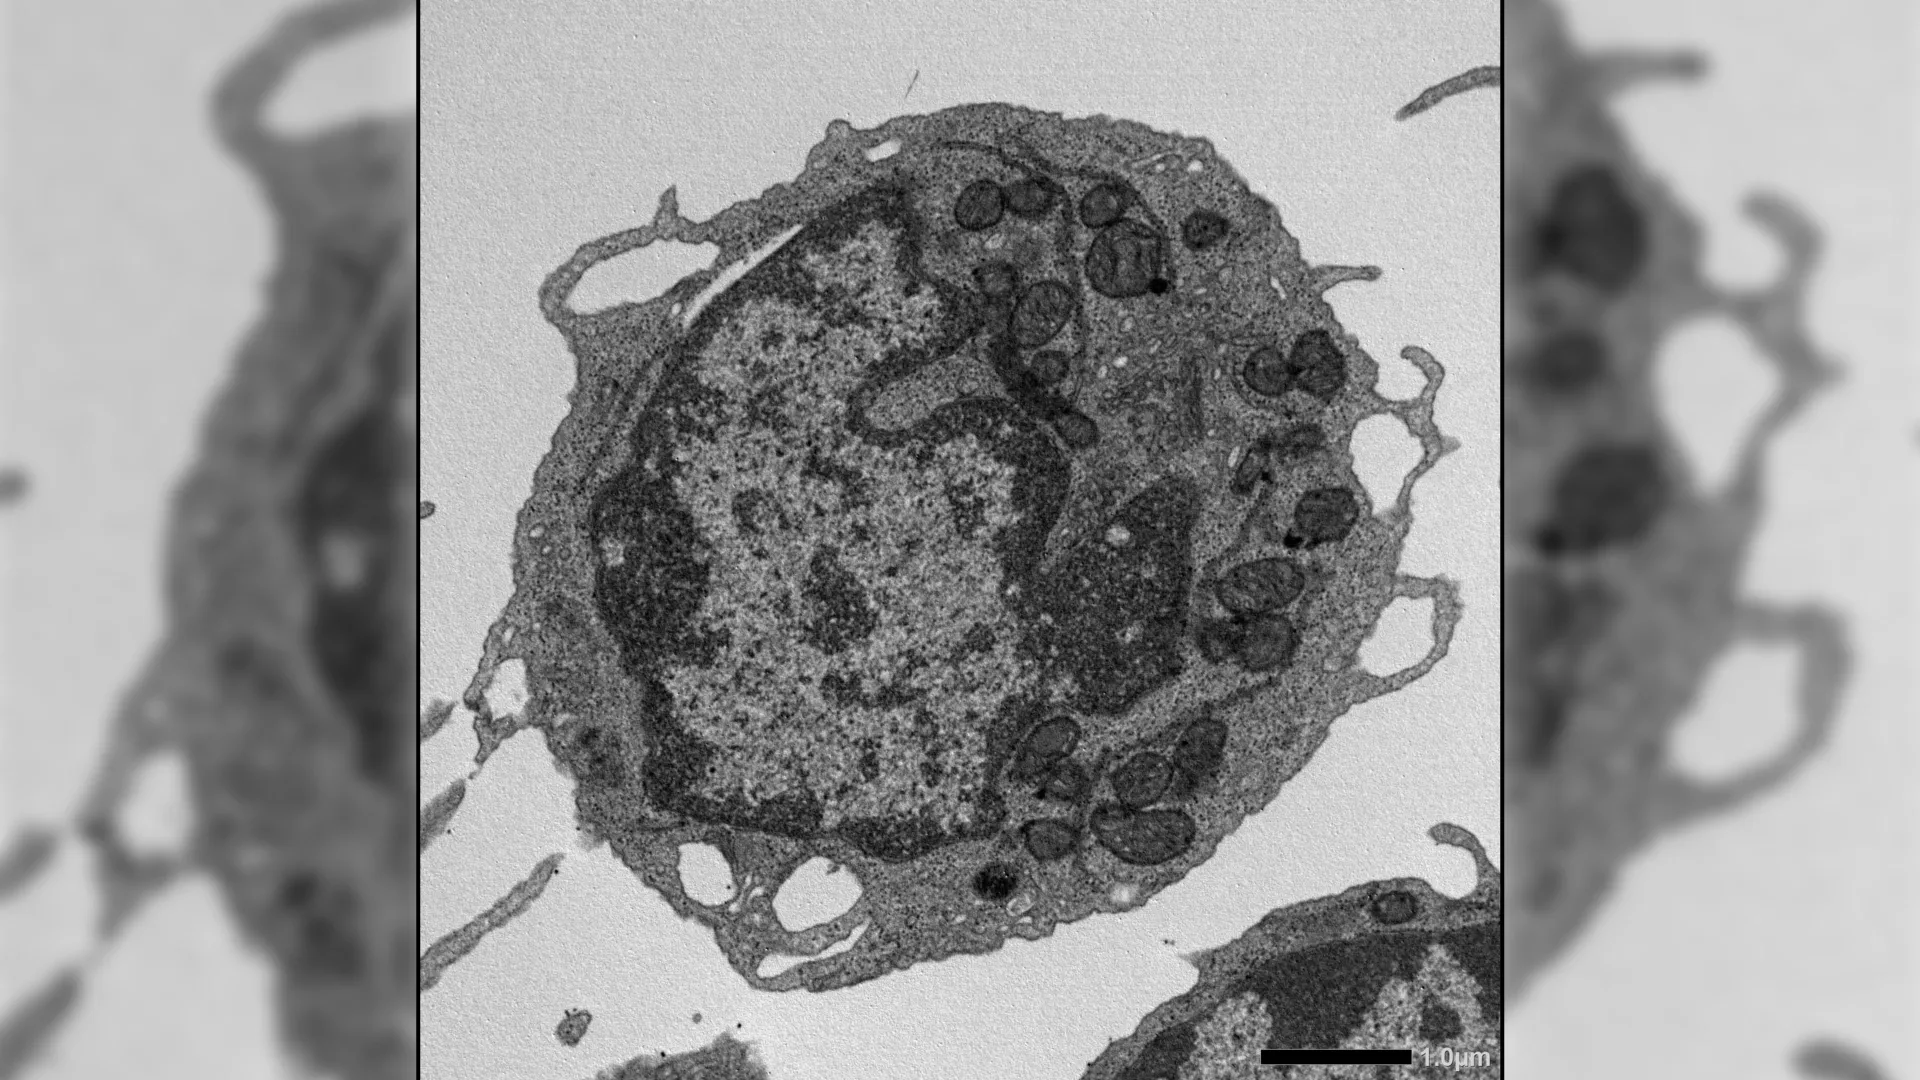

Outras técnicas fornecem insights mais profundos, incluindo citometria de fluxo, amplificação ex vivo, sequenciamento de RNA, análise de sequenciamento de cromatina acessível por transposase, imagens de alta resolução, testes metabólicos e estudos detalhados de mitocôndrias. Juntos, esses métodos permitem aos pesquisadores estudar como o MLKL afeta os HSCs em vários níveis.

Quando ativado sob estresse, o MLKL move-se brevemente para as mitocôndrias, as estruturas produtoras de energia dentro das células. Lá, causa danos ao diminuir o potencial da membrana, alterar a estrutura mitocondrial e reduzir a produção de energia. Esses efeitos levam a características-chave do envelhecimento das células-tronco hematopoiéticas, incluindo redução da capacidade de auto-renovação, diminuição da produção de linfócitos e uma mudança em direção à produção de células mieloides.